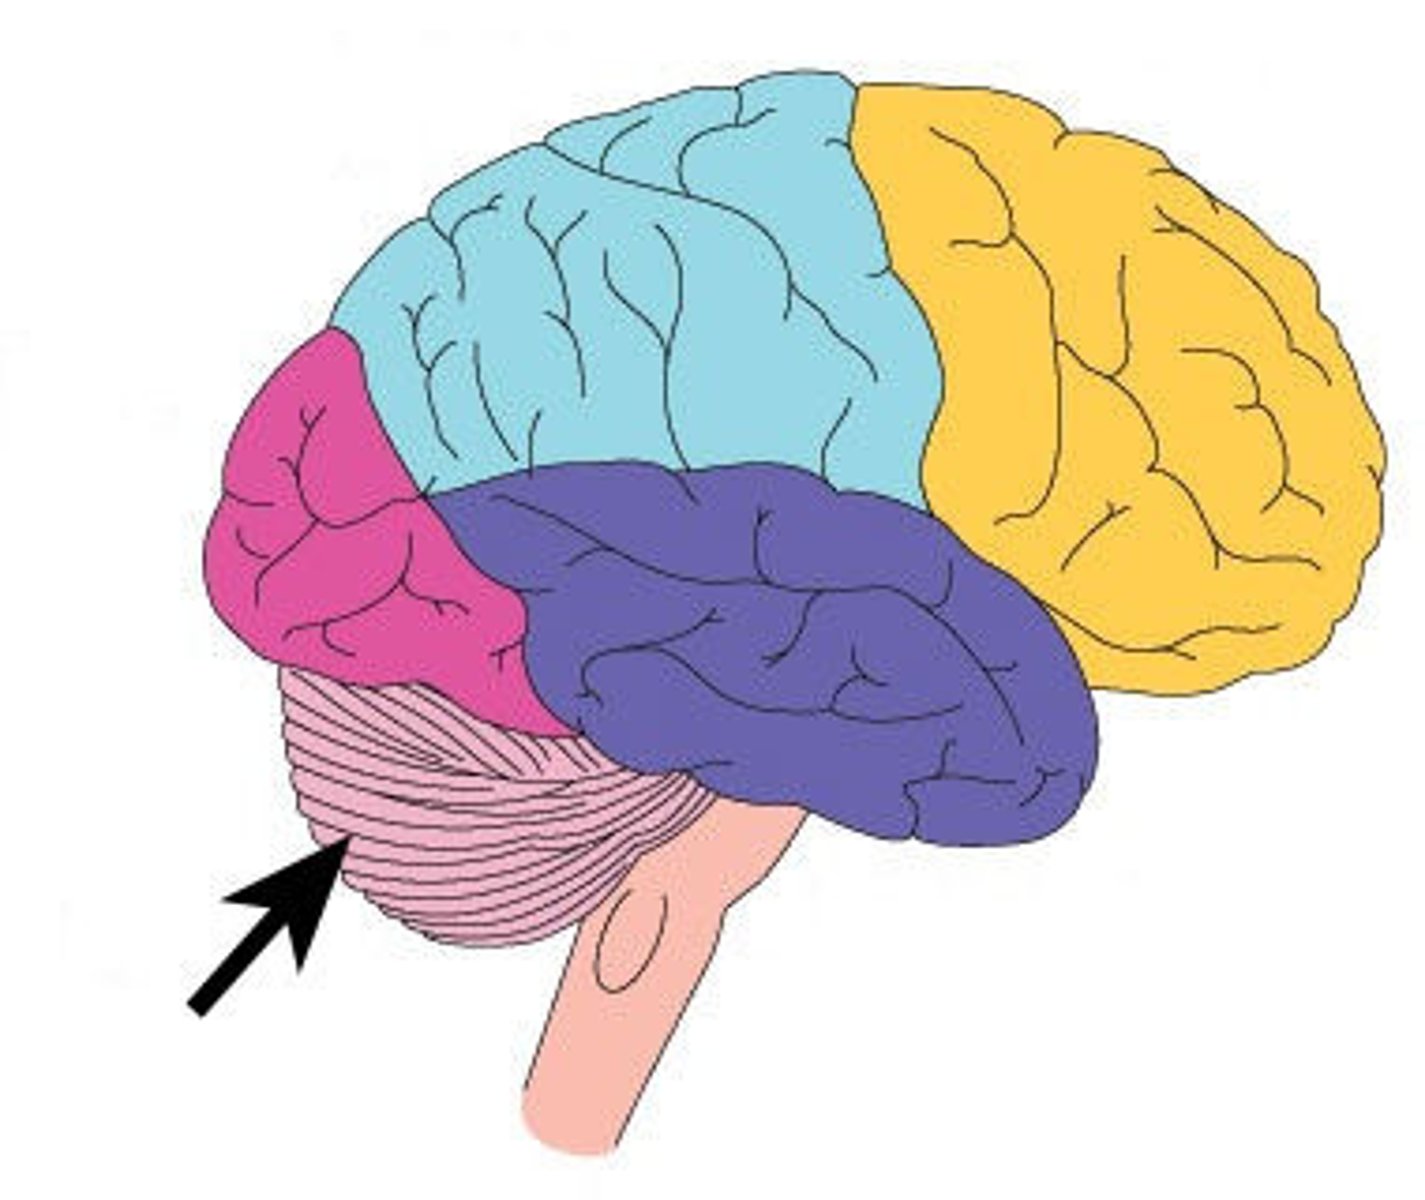

What are the four regions of the brain?

cerebrum, diencephalon, brainstem, cerebellum

frontal lobe function

higher intellectual functions (concentration, decision making, planning), personality, verbal communication, voluntary motor control of skeletal muscles

parietal lobe function

sensory interpretation of textures and shapes, understanding speech and formation of words to express thoughts and emotions

temporal lobe function

interpretation and storage of auditory and olfactory sensations, understanding speech

occipital lobe function

conscious perception of visual stimuli,

integration of eye-focusing movements, correlation of

visual images with pervious visual experiences

insula function

memory and interpretation of taste

frontal lobe location

parietal lobe location

temporal lobe location

occipital lobe location

insula lobe location